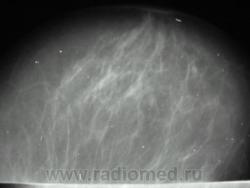

пациентка после травмы молочной железы, с 26.02.09 предъявляет жалобы на кровянистые выделния из правого соска. Осмотрена онкологом- посттравматическая гематома правой молочной железы, ПАБ материал получен из очага кровоизлияния. Делала мамографию, заключение из другой больницы- узловая фиброзная мастопатия правой молочной железы. А на УЗИ- дилятация мелких протоков в правой молочной железе, склерозированный лимфоузел в наружной области справа 11 на 5 мм. На данный момент беспокоят все те же выделения из правого соска, напрвили к нам на маммографию, боятся онкологию пропустить. Ваше мнение коллеги?

последние 3 снимка-архив 28.05.09 г. Женщина 1935 г.р.

И вот, вышло такие две серии:

А, ведь, какая-то "объёмка" вырисовывается.

врач Узи сказал, что исследование неинформативно для выявления внутрипротокового рака и ничего не выявил у данной пациентки. Коллега рентгенолог из соседнего города отозвался на помощь и предложил сделать пациентке дуктографию, результатом сказал поделится, а возможности сделать МРТ и КТ пока нет(((((((((((((((

Безусловно для выявления внутрипротокового рака необходимо произвести дуктографию. Нашей коллегой Рыбаковой Людмилой Александровной представлен прекрасный случай внутрипротокового рака.